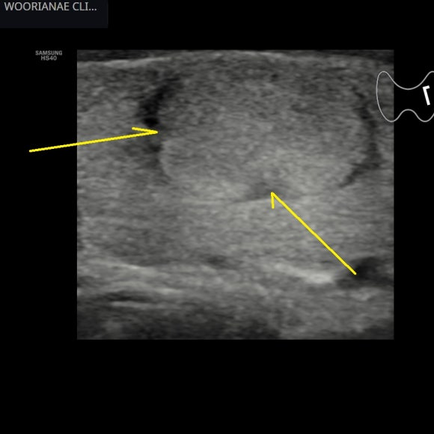

하복부, 골반 초음파; 난소종양

1시간 전

1분 분량